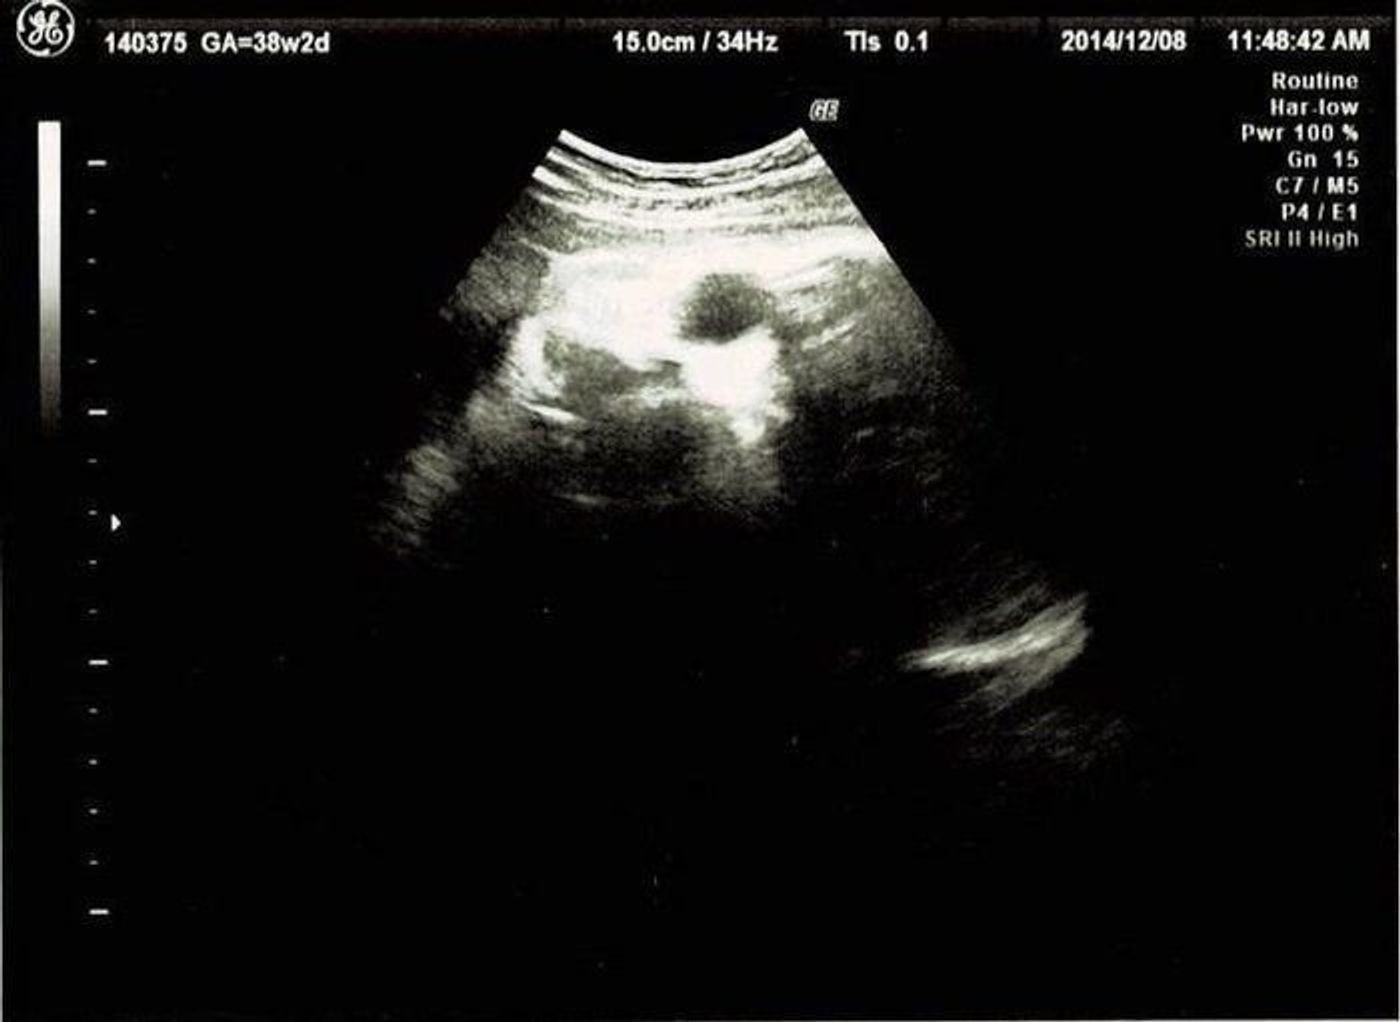

回答数: 4 件 現在31wの初産婦です。 30w6dの検診で、BPD 872、FL 548 FTA 533 とあり、Drから「頭が大きいけど、水頭症はなく、心臓、羊水、臍帯も問題ないから」と言われましたが、カルテには「第3脳室拡大? ? 脳梁欠損症の疑い。 経過観察」とありました。 これまでの健診でも(Drが毎回変わるものの)いつも頭が体と比べて2~3w分大きいです。 何か障害があるので頭の大きさと大腿骨の大きさが3か月以上も誤差が出てる。 fl 短い 頭大きい 胎児 色々調べました。 すると出てくる出てくる、色々な障害。 ダウン症か 軟骨無形成症かなぁと思い それからというもの 沢山の方のブログを拝見しました。

33週 胎児の頭がかなり大きくて不安です 本日33w0dで、37wで帝王切開の予定です。本日検診がありました。エコーで、BPDが38w、APTDが35w、FLが33w相当で体重が2409gと表示されており、医師からもかなり大きめだと言われました。妊娠中の気がかり(体重・食事・病気・体調など) Q 妊娠21週。 胎児の頭が大きく大腿骨が短いと指摘され、とても不安です。 (128) (妊娠週数・月齢)妊娠6か月 (〜23週) 21週目の妊婦健診で、胎児の頭が大きく、大腿骨が短いことを指摘されました 頭が大きい赤ちゃんをご出産されたお母さん方教えて下さい。 解決済 気になる 1 件 質問者: sugatti35 質問日時: 0937 回答数: 5 件 妊娠35週半ばの妊婦です。 先日定期健診へ行ったところ、エコーから先生が「太ももの骨の長さ(FL)腹部の面積(FTA)は標準なのに、頭囲(BPD)がえらい大きいなぁ・・」と言われました。 思わず「え"っ? ? 」と大きく聞き返したと

胎児エコーの結果、推定体重は1,751gになっていました。 胎児発育曲線と照らし合わせても、 ほぼ平均と言える まで近づいてきました(^v^) さきち 少しほっとできるね。 ただ、見ていたら 頭が週数よりだいぶ大きく測れていた ので、ここまでは大きく 2dよりも3d・4dエコー検査の方がいい? 胎児を見る場合、現在の2dエコー検査方法もかなり進化しており、 3dとあまり差はない と言われています。 しかし奇形に関しては3dの方が判断しやすいようで、口角亀裂も3dの発達で発見率が上がったとの事。